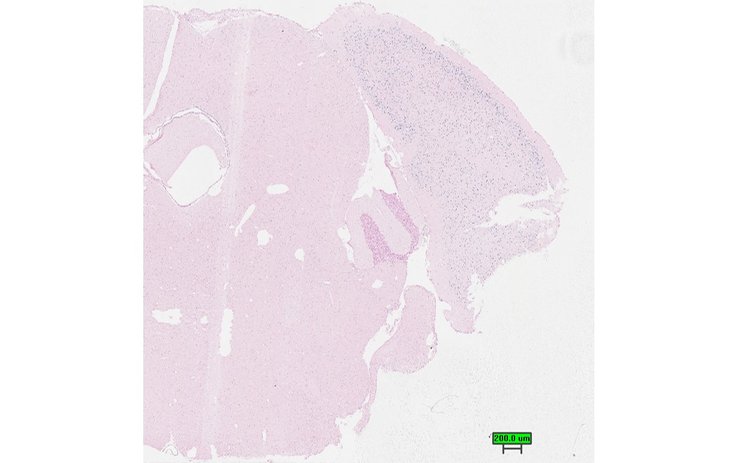

Specimen UC Davis_1862819: postnatal adult; Ctdspltm1.1(KOMP)Mbp/Ctdspl+ (more )

Structure Level Pattern Image Note

TS28: metanephros Present UC Davis_1862819 kidney

Specimen UC Davis_1862820: postnatal adult; Ctdspltm1.1(KOMP)Mbp/Ctdspl+ (more )

TS28: metanephros Present UC Davis_1862820 kidney

Specimen UC Davis_1862821: postnatal adult; Ctdspltm1.1(KOMP)Mbp/Ctdspl+ (more )

TS28: metanephros Present UC Davis_1862821 kidney